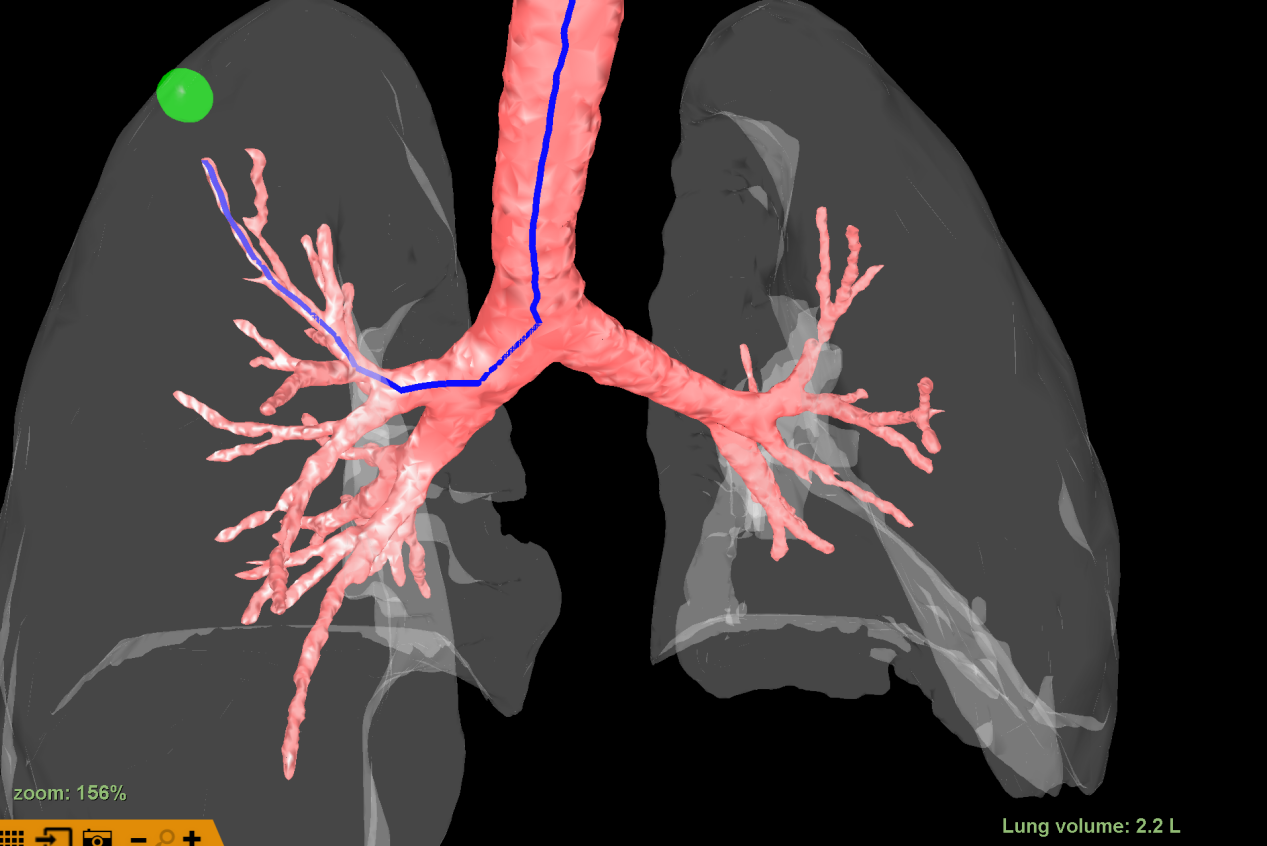

该病灶于右肺上叶尖段可见一磨玻璃结节,结节较小,且位置极高,常规器械滑行或手指触摸定位结节难度较大,为达到精准定位、精准治疗,且有效缩短患者手术时间目的。朱坤寿主任医师及林绍峰副主任医师术前充分讨论,利用Lungpro增强现实支气管导航术前三维重建支气管树,分析病灶与气道位置关系,拟定染色标记胸膜区域。

三维支气管树重建

手术中,麻醉科诱导麻醉后,手术团队采用外径4.0mm的支气管镜,根据支气管导航提供的路径抵达既定位置(RB1亚亚支,约第6级气道),往前推送打药管至病灶附近胸膜处,于此处打入0.2ml美兰染色液,随后缓慢推入空气让染色液逐渐渗透至病灶附近胸膜区域。

导航路径